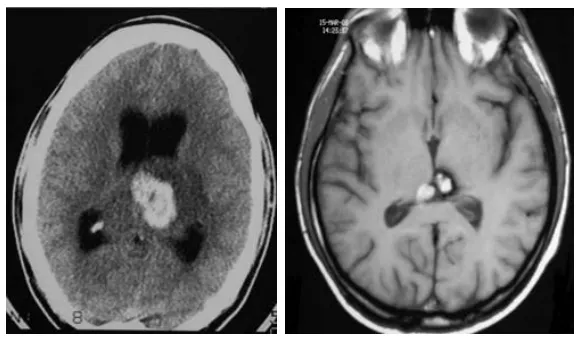

26岁男性因突然头痛、呕吐和意识恶化就医。CT扫描显示间脑后部出血性病变(图1左)。诊断为丘脑肿瘤,给予40Gy分次外束放射治疗。放疗后脑室增大,并插入脑室-腹膜分流器。放疗一...